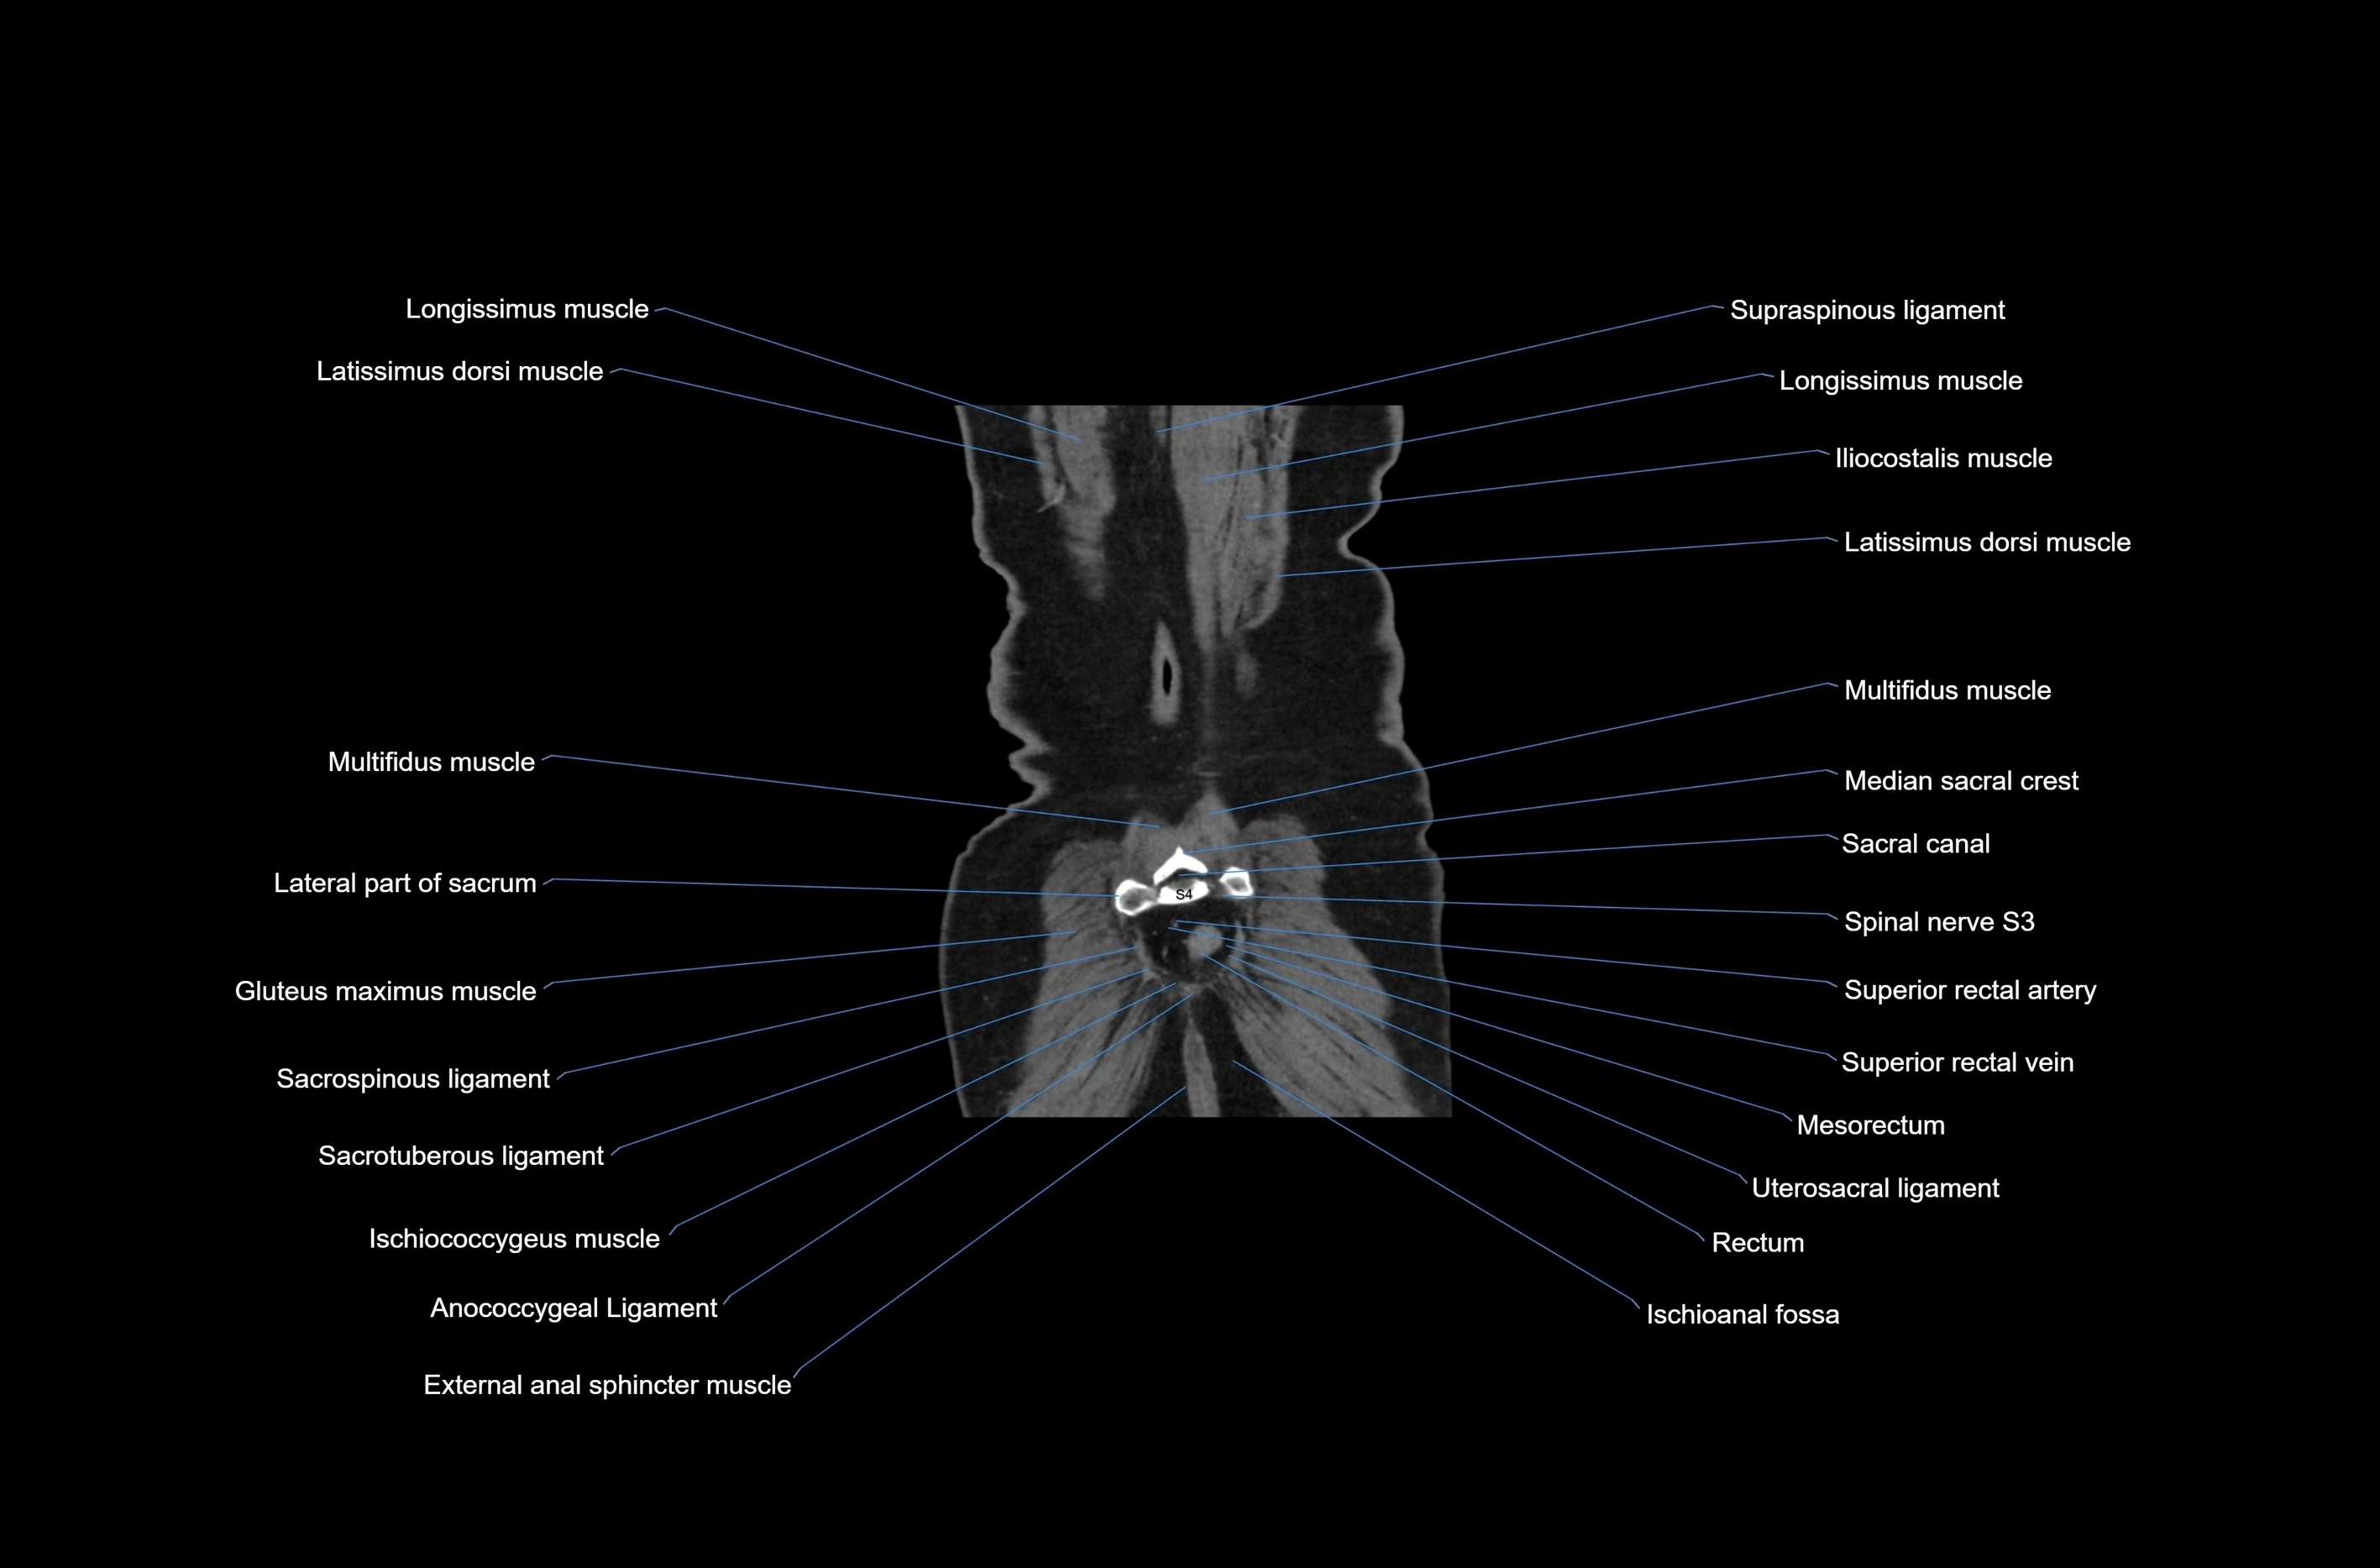

CT images